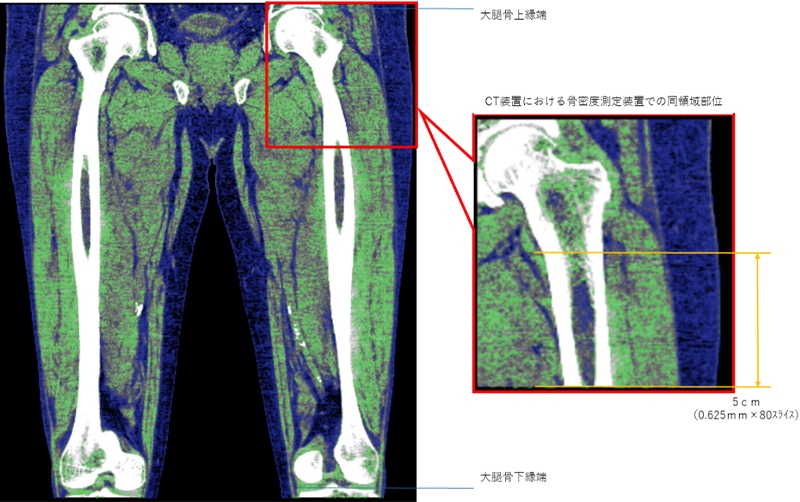

CT装置での体組成範囲は、骨密度装置での測定における同一範囲とした(図3)。また、筋肉および脂肪のCT値は筋肉;20~100、脂肪;-150~0を抽出した値とした。測定側大腿骨頚部にインプラントがある、下肢動脈に石灰化がある、測定体位をとれない、医師または測定技師が測定不可と判断した者は除く。

撮像条件;64ch×0.625㎜、120kV、ACE(SD13、5㎜スライス)、BP1.1、F32IP3、平均DLP956.2±24.4 m㏉・㎝

解析画面;0.625㎜スライス

解析範囲;図2参照

解析方法;WSの機能で決められた脂肪および筋肉のCT値の範囲を抽出し体積を測定する

図3 CT測定範囲(大腿部全体と骨密度測定装置での同領域部位)